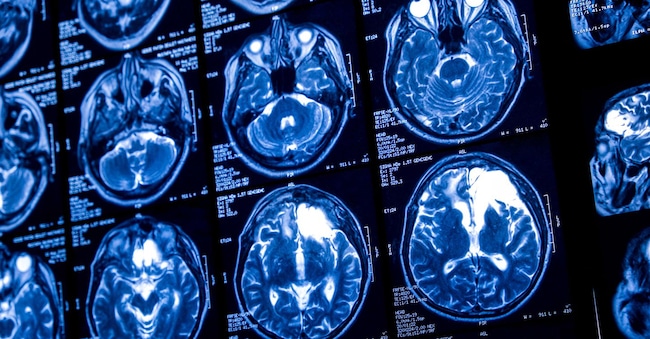

Brain gliomas, what they are and how to tackle them with precision oncology

Gliomas are the most common tumours of the central nervous system in adults. Every year there are more than 3,000 new cases in Italy. But they are not all the same. Among these neoplasms, low-grade gliomas with mutations in the Idh genes are rarer, representing true orphan diseases. But science is advancing. And it offers increasingly significant prospects even for the most complex cases. It is essential to know the pathologies and the possibilities of approach, in a field where knowledge is still very fragmented. To fill these gaps, the Aiom Foundation (Italian Association of Medical Oncology) launched a national online training and information campaign in recent months, as part of a project implemented with the unconditional contribution of the Servier Group in Italy.

'Even for the treatment of gliomas, in particular low-grade gliomas, precision oncology can be used, which may reshape clinical practice in the near future,' points out Enrico Franceschi, director of Nervous System Oncology at the Irccs Istituto delle Scienze neurologiche in Bologna. 'It is very important to check for the presence or absence of Idh1 and Idh2 mutations.

Why is it important to recognise these cellular characteristics? Because biomarkers indicate specific pathologies characterised by a decidedly more favourable prognosis and greater sensitivity of gliomas to radio and chemotherapy. In short, they allow therapy to be personalised as much as possible. 'At the time of diagnosis it is therefore essential to carry out some molecular tests early on in order to best identify the different subtypes of gliomas,' Franceschi recalls. 'Among the new generation therapies is also vorasidenib, an oral Idh1 and Idh2 inhibitor drug that has proven to be an effective treatment in postponing radio and chemotherapy in low-grade gliomas and is a significant medical-scientific innovation.